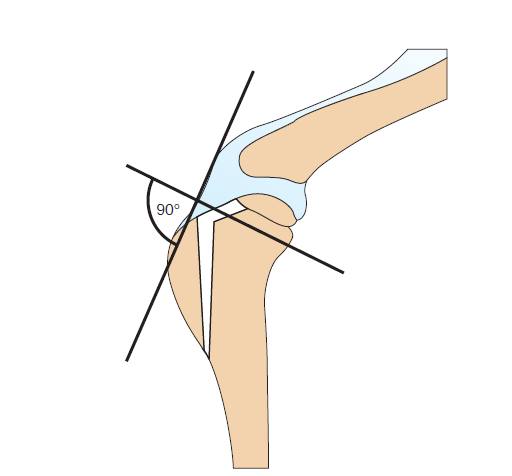

TTA(tibial tuberosity advancement) представляет собой остеотомию большеберцовой бугристости, которая не несет весовой нагрузки. Остоетомия выполняется таким образом, что достигается угол в 90 градусов между склоном плато большеберцовой кости, тем самым нивелируется тяга каудального смещения бедренной кости, и опять же необходимость в передней крестообразной связке отпадает.